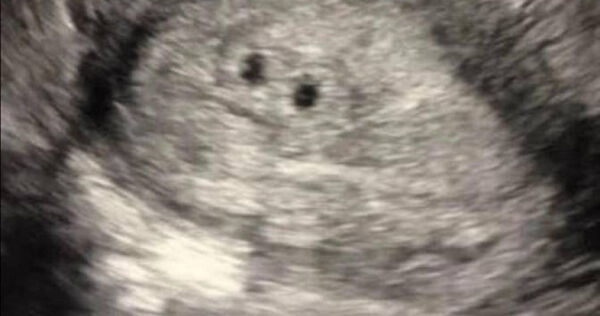

▲國外一名媽媽以為懷三胞胎,最後卻只生出1個寶寶。(圖/翻攝自vfbabygirl28 TikTok)

懷孕是喜事一樁,但如果發生意外,心情可能會受影響。國外一名媽媽以為自己懷了三胞胎,然而第3次產檢時,卻只剩1個寶寶,另外2個被「吃掉」了,讓她十分震驚。

TikTok用戶「vfbabygirl28」分享懷孕期間情緒有如雲霄飛車般的經歷,第1次產檢時掃描被告知懷了雙胞胎,然而當她第2次檢查,情況卻有所轉變,這次她發現自己懷了三胞胎,為此感到又驚又喜。

只不過結果令人失望,因為第3次檢查發現,其中2個寶寶完全消失,「這傢伙吃掉了他的兄弟姊妹!我的天哪!」最後她分享1張新生嬰兒的照片,看起來臉色紅潤很健康,但原本的三胞胎只剩下1個。